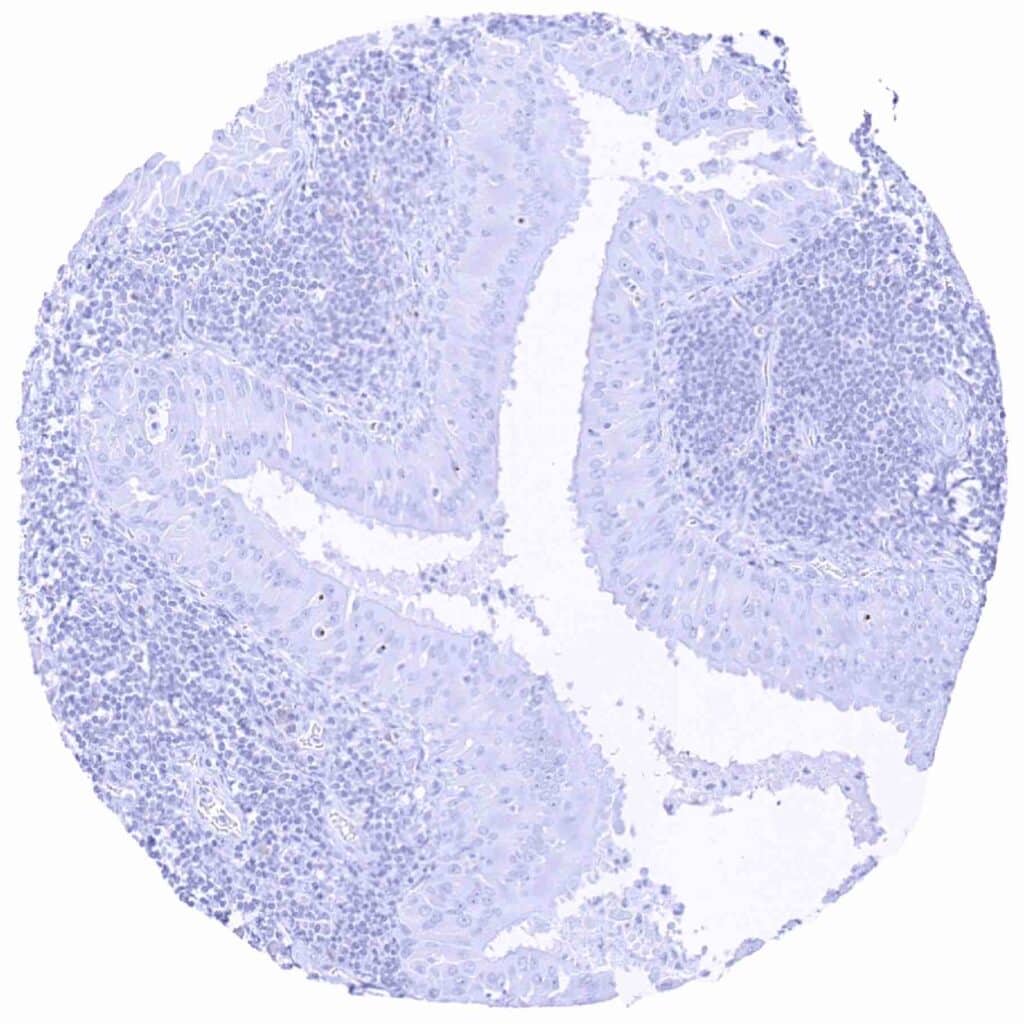

Testis – Prostein negative seminoma